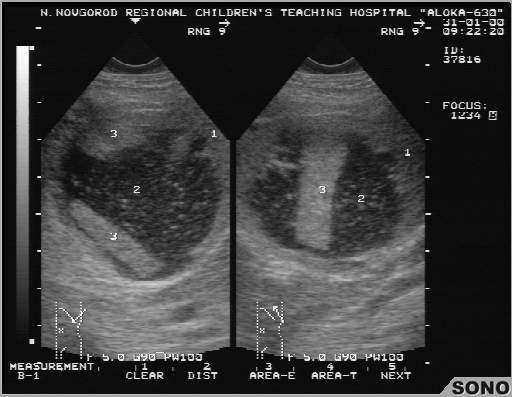

Травматический разрыв капсулы селезенки с образованием ограниченной гематомы брюшной полости